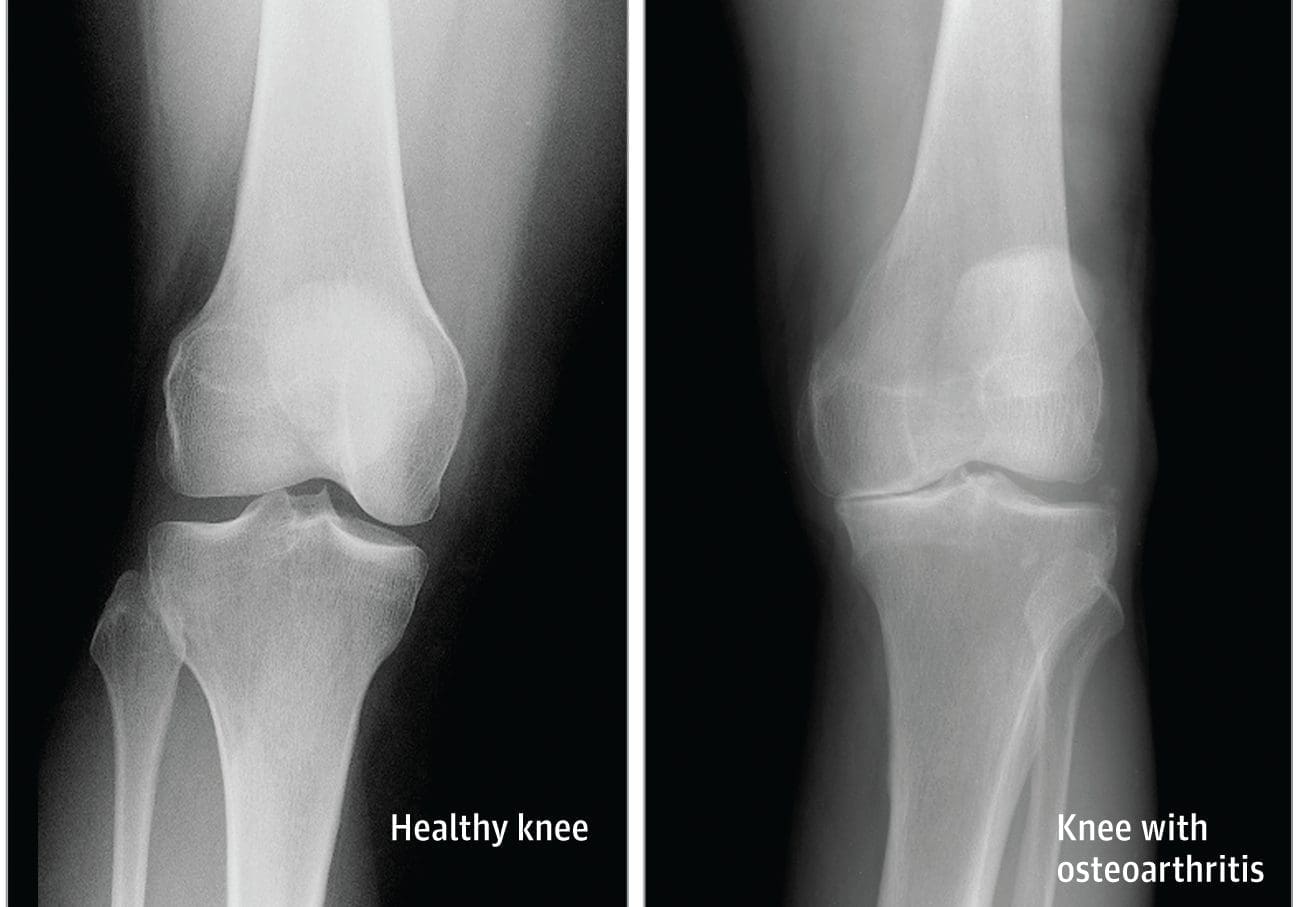

Osteoarthritis is the most common type of arthritis which affects the knee joint. This form of arthritis is a degenerative, wear-and-tear health issue which occurs most commonly in people 50 years of age and older, however, it may also develop in younger people.

In osteoarthritis, the cartilage in the knee joint gradually wears away. As the cartilage wears away, the distance between the bones decreases. This can result in bone rubbing and it can create painful bone spurs. Osteoarthritis generally develops slowly but the pain may worsen over time.

• X-rays. These imaging diagnostic tests produce images of compact structures, such as bones. They can help distinguish among various forms of arthritis. X-rays for knee arthritis may demonstrate a portion of the joint distance, changes in the bone as well as the formation of bone spurs, known as osteophytes.